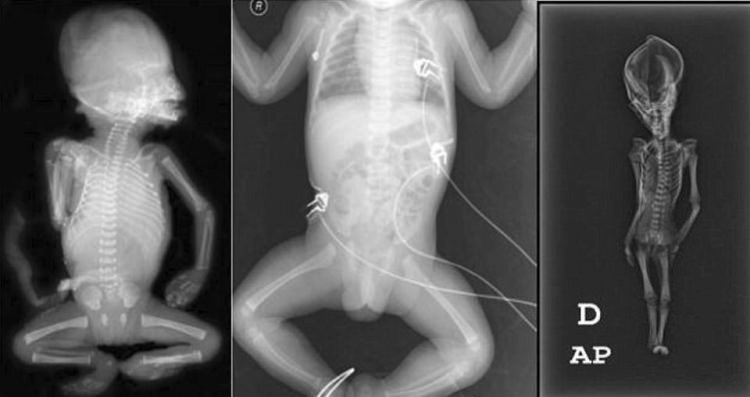

2003 yılında, Şili'deki Atacama bölgesinde, deri bir çanta içerisinde terk edilmiş bir kilisede bulunan, koni şeklindeki bir başa ve 15 cm uzunluğa sahip mumyanın bir uzaylıya ait olabileceği iddia edilmişti.

İspanyol bir koleksiyoncu tarafından satın alınarak ortaya çıkarılan mumya ile ilgili daha önce Sirius isimli bir belgesel çekilmiş, çeşitli komplo teorilerinin yanı sıra bulunan iskeletin uzaylıların varlığına kanıt olabileceği öne sürülmüştü.

Uluslararası bir bilim ekibi 15 santimetre büyüklüğündeki mumya üzerinde yaptığı araştırmayı tamamladı ve mumyanın 15 haftalık bir cenine ait olduğunu açıkladı.

California Üniversitesi, San Francisco Üniversitesi ve Stanford Üniversitesi tarafından "Ata" ismi verilen mumyaya yapılan DNA analizleri, ,gizemini uzun süre koruyan kalıntının, çeşitli genetik mutasyonlara uğramış, 6-8 yaşında olduğu tahmin edilen cüce bir kız çocuğuna ait olduğunu ortaya koymuştu.

Yapılan bilimsel çalışmalar, çocuğun 40 yıl önce öldüğünü ve bugüne kadar tanımlanmamış olan gen bozukluklarına sahip olduğunu açığa çıkarmıştı.

Diğer taraftan "Ata"nın 6-8 yaşına ulaşıp ulaşmadığı bilinmiyor. Bilim insanları, çocuktaki genetik bozukluğun rahim içindeyken de kemiklerinin büyümesine neden olabileceğini, bu yüzden mumyanın prematüre bir bebeğe de ait olabileceğini düşündüklerini bildirmişti.